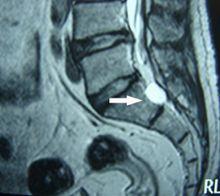

腰椎腸源性囊腫診斷與鑑別診斷

本病的診斷可根據病人為男性兒童或青少年;以根性疼痛起病,計較快地出現脊髓壓迫症;病程中有間隔數月或數年的反覆發作,如發現有其他先天性畸形,即應考慮有腸源性囊腫,應及時做椎管造影或MRI檢查明確診斷。 在鑑別診斷上需注意與以下椎管內囊性疾病區分: 蛛網膜囊腫 多見於青年人,女性多於男性,好發於胸段脊髓的背側,臨床表現以胸背部疼痛為主,並逐漸出現雙下肢感覺。運動障礙。在坐位或立位時症狀明顯或加重,臥位時症狀緩解。病變部位棘突有壓痛和叩擊痛。腦脊液壓力不高,椎管腔有不全性或完全性梗阻,細胞數正常,蛋白含量輕度增高。脊椎x線平片多無改變,脊髓造影可呈囊狀充盈缺損,俯臥位造影為陰性,仰臥位造影為陽性,仰臥位或立位時才顯示囊腫陰影。MRI檢查顯示脊髓背側梭形囊狀占位,在T1加權像上為一塊狀軟組織強度的信號影.加權像上為高強度信號,增強掃描多無強化。 脊髓蛛網膜炎 起病緩慢,症狀時輕時重.多在外傷或感冒發熱後起病。感覺障礙比較明顯,感覺改變區域的分布常不規律,無明顯的感覺障礙平面。一般運動障礙和括約肌障礙較輕或不明顯。病程多有被動,並有較長的緩解期,呈多灶性體徵。脊髓造影呈散在點狀、片狀或燭淚狀和囊腫充盈缺損。 皮樣囊腫或表皮樣囊腫 多見於小兒,好發於下胸椎以下的圓錐、馬尾部。多位於脊髓外硬骨膜內,常並發脊椎裂。囊腫所在部位有竇道、多毛、血管痣等各種皮膚異常。腦脊液蛋白含量明顯增高。x線檢查可顯示椎管擴大、椎弓根變扁、椎體後緣有向內的壓跡。MRI檢查皮樣囊腫中含有蛋白,故在T1加權像上信號略高於腦脊液,在T2加權像上呈高信號,與腦脊液相似。而表皮樣囊腫在T1與T2加權像上的信號均與腦脊液相似,但囊腫邊界光滑,呈圓形或卵圓形,可見壓迫脊髓和馬尾的表現。